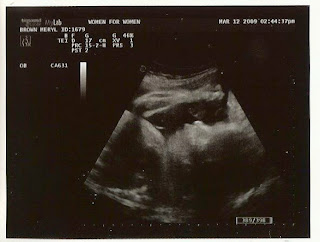

A wonderful profile shot… She was opening and closing her mouth, but we caught her while closed.

She is showing us her fist and arm at the top… and it looks as though her mouth is open.

Fist through foot! She has giant feet… must take after daddy… Her fist is so powerful that she can break through body parts!